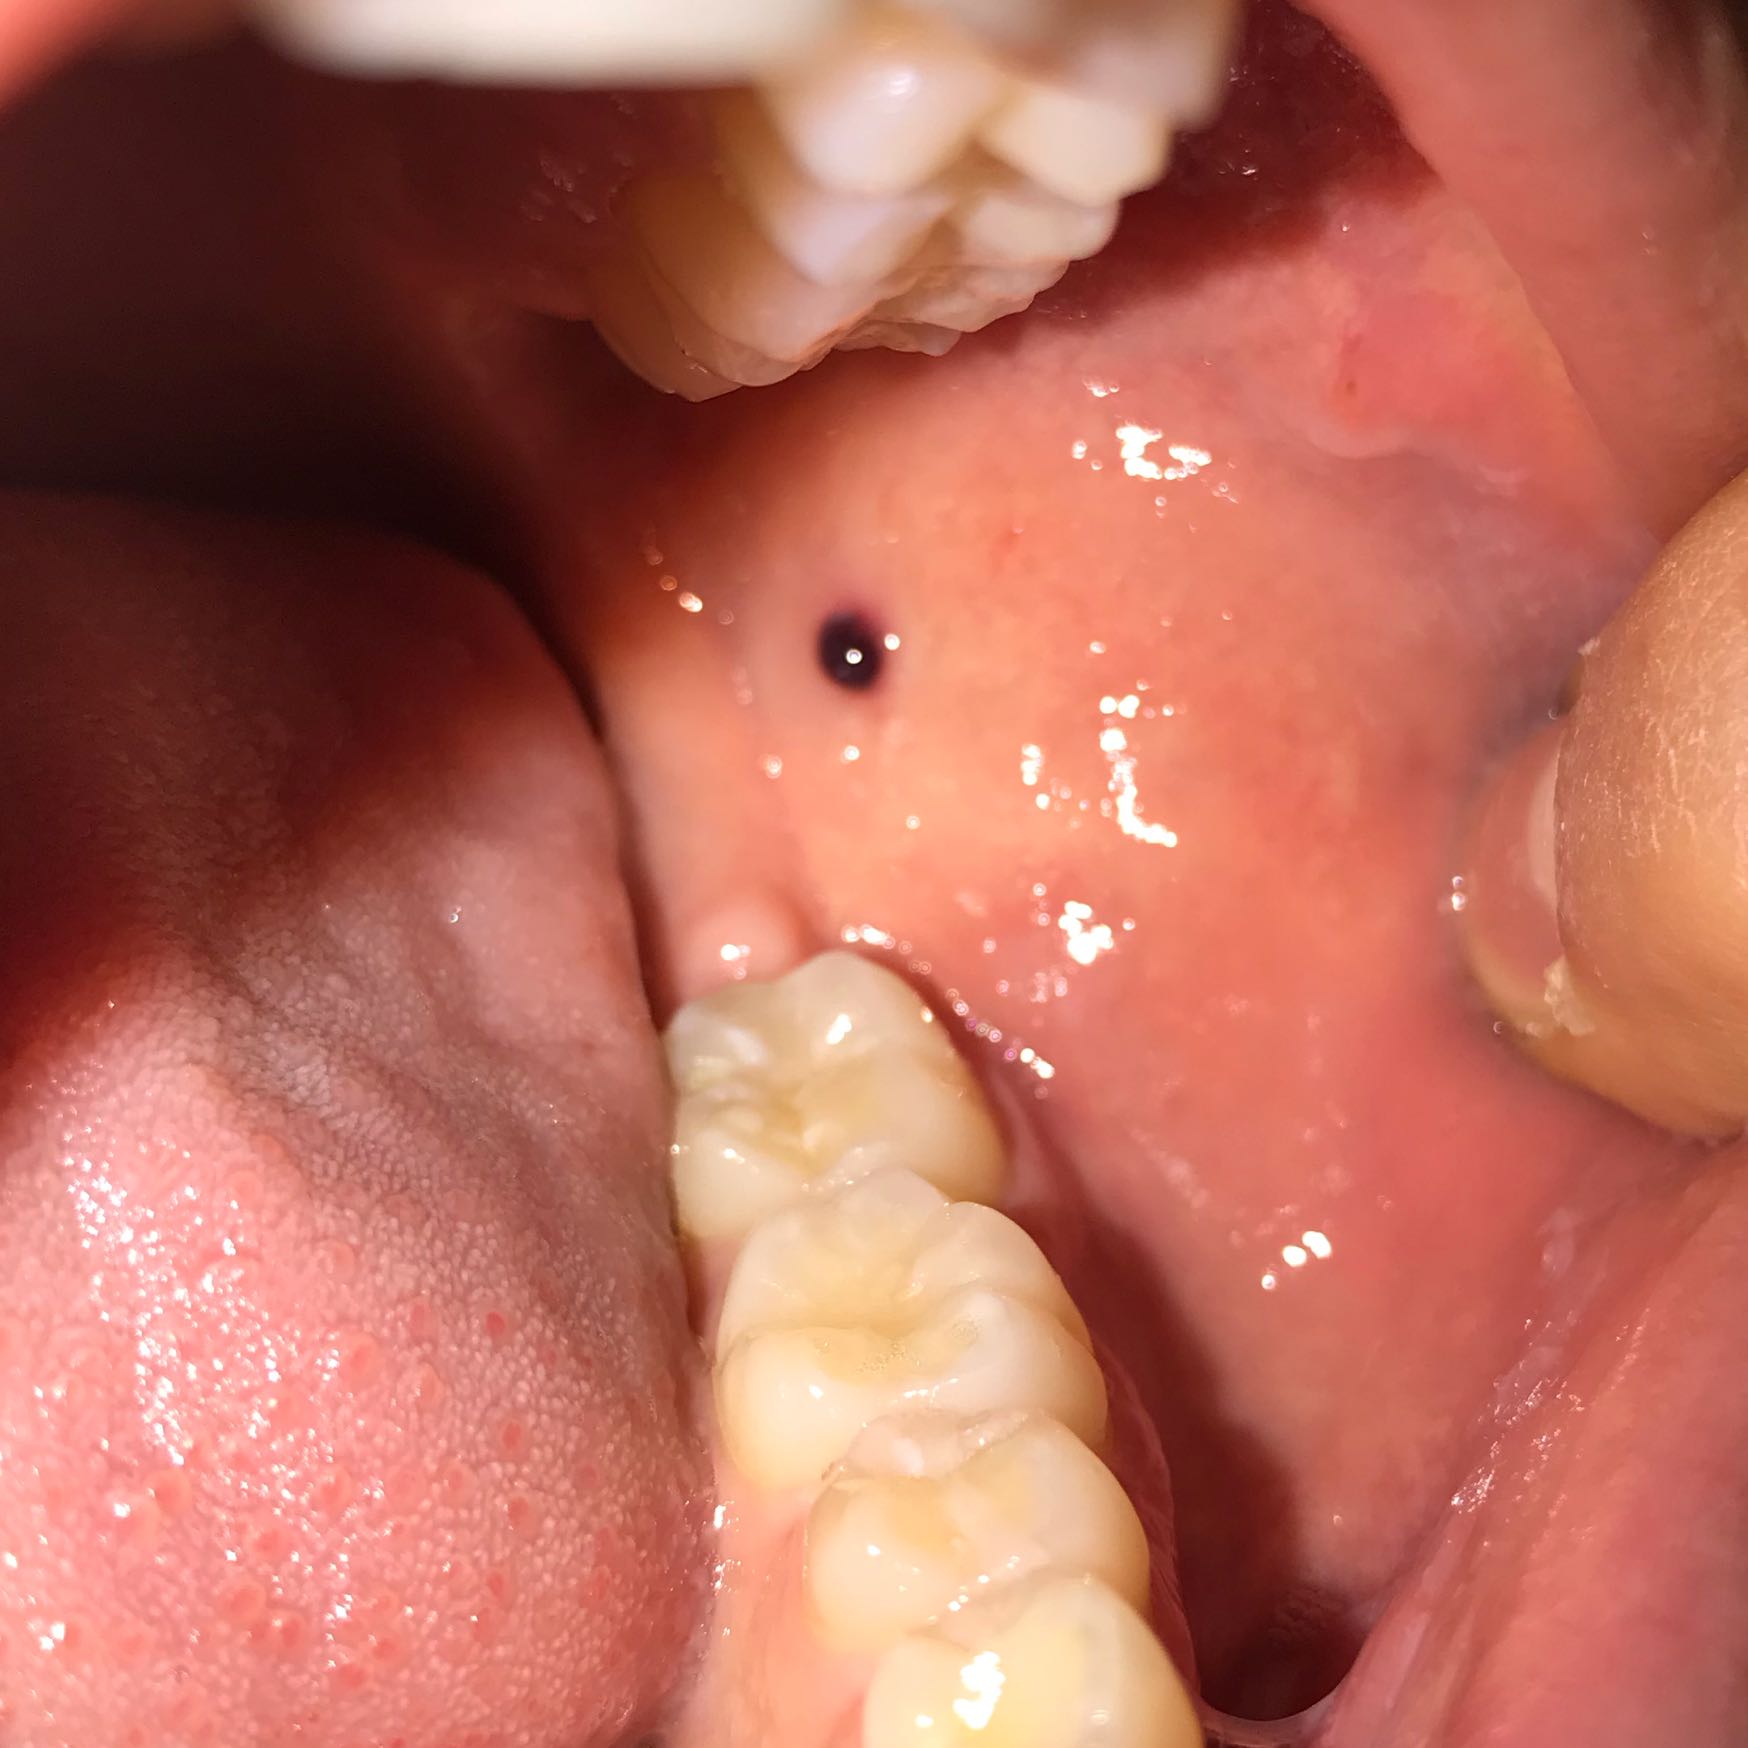

Schwarzer punkt im Mundraum bekommen was ist das siehe ( Bild )? (Gesundheit, Gesundheit und